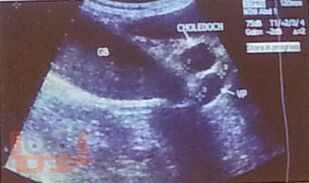

В учебном пособии представлена диагностика острого холецистита по данным ультразвукового исследования. Особое внимание уделено оценке положительных и отрицательных эхографических признаков острого холецистита на фоне проводимой терапии.